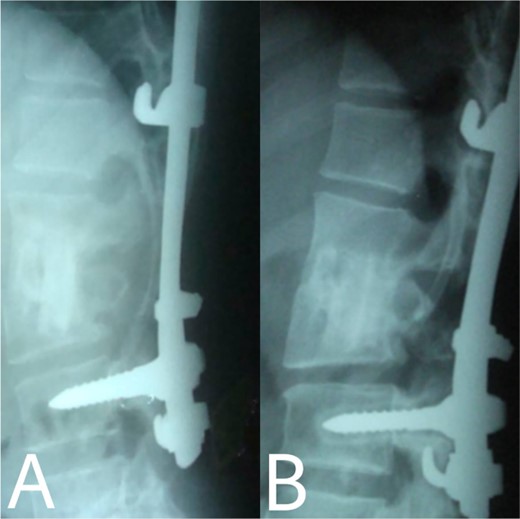

A 24-year-old farmer female was admitted to the Department of Neurosurgery with low back pain, no fever, cough, motor deficit, or any symptoms. Medical, surgical, family histories and physical examinations were unremarkable. The laboratory findings showed a white cell count of 9.8 × 103/μL, C-reactive protein concentrations of 20, erythrocyte sedimentation rate of 50 mm/1 h, 90 mm/2 h and tuberculin skin test was positive. X-ray films showed the collapse of the L1, L2 vertebrae, and L1–2 intervertebral space (Fig. 1). An abscess was observed at the L1–L2 vertebral level in lumbar magnetic resonance imaging (MRI) (Fig. 2). Chest X-rays and Sputum smear were negative. The patient was treated with anti-TB treatment (Isoniazid, Rifampicin, Ethambutol, Pyrazinamide) due to spinal TB findings on MRI (Fig. 3). After 40 days, the patient was diagnosed with grade 1/5 lower limb weakness, and bladder and bowel dysfunction, with no impairment in sensation, which predicts spinal infection. MRI confirmed these abnormalities and showed typical findings such as vertebral endplate destruction, bone marrow and disk signal abnormalities, and paravertebral or epidural abscesses (Fig. 3). Due to clinical manifestations and MRI spinal TB findings (Fig. 3), the patient underwent surgical debridement, interbody fusion and internal fixation with fibular autografting and supplemental posterior spinal stabilisation using a posterior-only approach. On post-operative follow-up, the treatment continued for 9 months, in addition to physical therapy for lower limb weakness. In the end, the patient returned to full motion with grade 5/5 in the lower limb, normal sensation, and no bladder or bowel incontinence. No recurrence was observed in the grafting area. Radiologically 2, 6 and 12 months, 14 years’ post-operation, the patient had achieved full bony graft spinal fusion (Figs 4–6).

(A, B) Complete bony incorporation between the implanted fibular autograft and host vertebral body was noted on the lateral radiograph 1, and 14 years later.

Even though a spinal epidural abscess is a rare infectious situation, its incidence is increasing due to risk factors such as chronic illnesses, immunodeficiency states and drug abuse. MRI is an effective diagnostic test for spinal infection and to differentiate between TB and pyogenic spondylitis. It is difficult to determine the diagnosis when there are atypical manifestations of infectious spondylitis. However, in our case, MRI demonstrated the typical finding such as the compression of the spinal cord by the two vertebral endplates destruction, the epidural abscess, the disk signal and bone marrow abnormalities. Conservative therapy is the basis of spinal TB treatment. This approach is insufficient in some cases that require surgical interventions [4]. When indicated, delayed surgical management may lead to a bad prognosis [5]. As in our case, the paraparesis developed after 40 days of TB drug administration. These aspects necessitated surgical procedures to prevent further spinal cord compression [6]. Surgical techniques included posterior approach decompression, abscess resection, bone grafting and instrumentations. Spinal TB primarily impacts the anterior elements due to its blood supply profusion. Hence, the conventional approach has long been to use the anterior approach in spinal TB treatment [6, 7]. A prospective study has shown that the anterior approach has good results in a minimum period of a 3-year follow-up. Also, Ge et al [8]. reported a case of spinal TB involving the L1 vertebra with a massive paravertebral abscess. They used the anterior approach in the decompression and grafting with posterior instrumentations and their results were satisfactory. However, in recent years, the posterior approach proved its advantages, including its familiarity, enough space for an adequate debridement of the focal lesion, in addition to less surgical invasion. Both approaches lead to reduced operation duration and fewer rates of complications [9]. On the other hand, the anterior approach has its risks, such as abdominal visceral injury, and neural and vascular injuries. Moreover, spinal instability may occur [10]. As for grafting, we used an autogenous bone graft from the fibula for osseous loss, which may be considered a golden standard, because of its immune correspondence and osteoinductive capability [4]. There are considerations about inserting a bone graft in an infected site, like the surrounding tissue’s capability to provide the biological background for recovery. The presence of biomechanical stability enables biological reactions to enhance bone ingrowth [11]. Bansal et al. reported the fibular strut graft efficacy along with cancellous graft in an anterior approach and without instrumentations [12]. Singh et al. also showed the same results but without cancellous graft [7]. In our case, the bone graft was supported with the posterior (T10–L3) hooks combination and screws. Spinal cord decompression is the priority. Besides, the infected extracted tissues had to be replaced with another component for the spinal column stability. The X-ray showed a successful fusion post-operation. The medication was administered for 9 months to prevent the recurrence of the infection [13]. After treatment, the muscle strength became 5/5 up from the pre-operative 1/5. Within 14 years of follow-up, the X-ray demonstrated a good bone fusion and the patient’s status was good (Fig. 6). Minimally invasive spinal surgery (MISS) has been used increasingly over the past two decades [14]. MISS is performed using smaller incisions instead of traditional open approaches to accomplish spine surgical operations. MISS includes spinal endoscopy and robotics, which has improved the accuracy of instrumentation placement and virtual/augmented reality that has been very helpful for practicing surgical skills without patients. These techniques decreased the sedation requirements, blood loss and hospitalisation time [15]. In conclusion, early diagnosis of TB spondylitis with proper treatment and surgical intervention immediately after a neurological deficit can protect the patients from the chronic spinal deformity. The posterior approach was sufficient and effective in our case. However, the surgical procedure should be planned on a case-by-case basis. Fibular graft and instrumentations were effective, although they were inserted on an infected background.